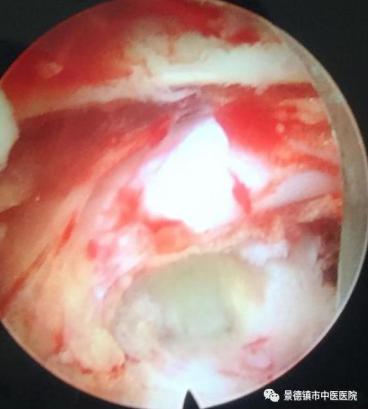

神經(jīng)根徹底減壓

術(shù)中成型后的骨塊及摘除的髓核